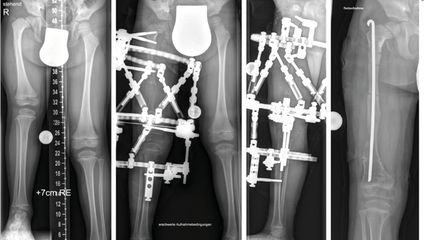

Angeborene Fehlstellungen des Unterschenkels

Kongenitale Deformitäten des Unterschenkels gehören zu den seltenen, aber medizinisch bedeutenden und operativ herausfordernden Diagnosen der Kinderorthopädie. Eine differenzierte ...

Korrektur assoziierter Gelenkspathologien beim kongenitalen Femurdefekt

Der kongenitale Femurdefekt ist eine der spannendsten und komplexesten angeborenen Fehlbildungen in der Kinderorthopädie und in der klinischen Präsentation sehr vielgestaltig. Während ...